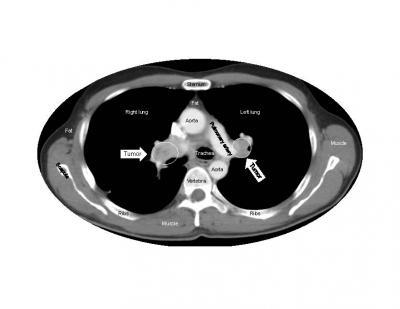

(Photo Credit: Cell Reports, Blagoev et al.)